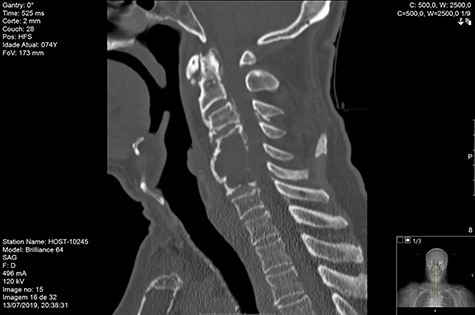

MRI and CT scans performed at 90 days post-radiation therapy showed an arrest of further progression of instability and resolution of the lytic lesion (Figs 7–13).

Computed tomography (CT) (Figs 1–3) and magnetic resonance imaging (MRI) (Figs 4–6) of the cervical spine were performed and revealed a lytic lesion involving most of C4, C5 and C6 vertebral bodies with bilateral extension to the posterior spinal elements of C4 and C5 and complete disruption of C4-C5 and C5-C6 intervertebral discs.

The Spinal Instability Neoplastic Score (SINS) [4, 6, 7] for assessing spinal instability from metastatic disease was used and the lesion was deemed unstable (SINS 13), with impending risk of increased neurological damage.